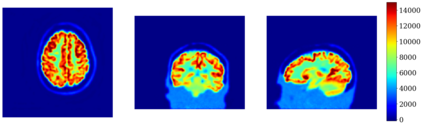

In this work, we investigate hybrid PET reconstruction algorithms based on coupling a model-based variational reconstruction and the application of a separately learnt Deep Neural Network operator (DNN) in an ADMM Plug and Play framework. Following recent results in optimization, fixed point convergence of the scheme can be achieved by enforcing an additional constraint on network parameters during learning. We propose such an ADMM algorithm and show in a realistic [18F]-FDG synthetic brain exam that the proposed scheme indeed lead experimentally to convergence to a meaningful fixed point. When the proposed constraint is not enforced during learning of the DNN, the proposed ADMM algorithm was observed experimentally not to converge.